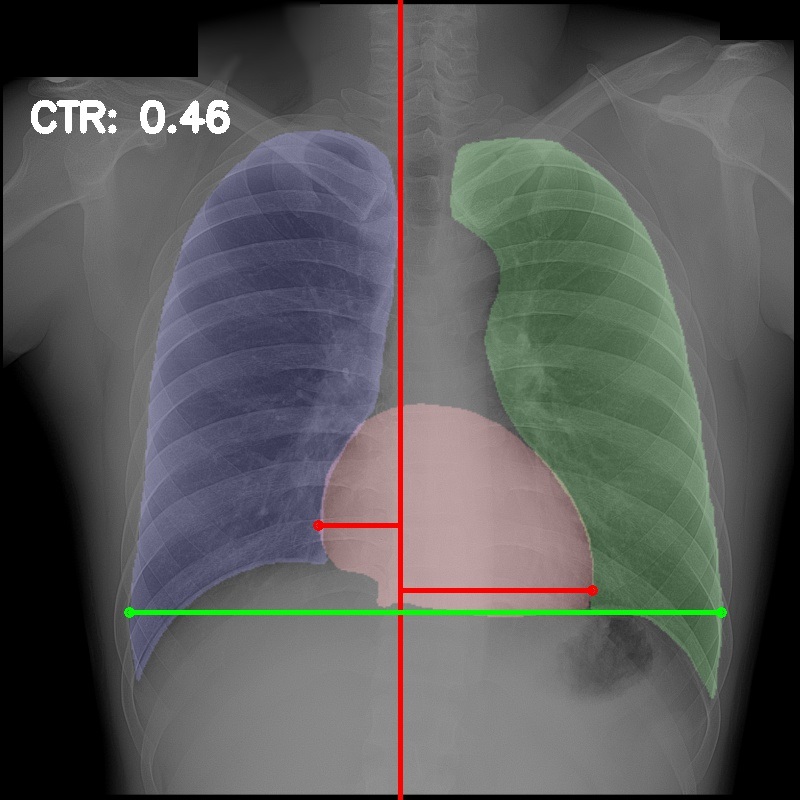

3.5 Cardiothoracic Ratio Calculation

After obtaining the masks, we calculate CTR with equation 1. We calculate cardiac diameter, , by finding the extreme points on the x-axis of the heart mask and calculate their x-axis distance. Thoracic diameter, , is calculated from extreme points from the lung mask. Figure 4 demonstrates the calculation of each component.

After obtaining heart and lung segments, we calculated , , and and marked them on the image along with CTR value calculated from Equation 1.

Figure 6 shows examples of our CTR calculation, where CTR values along with their , and measurement points are correctly identified. In this image, cardiomegaly is correctly detected by CTR value of .